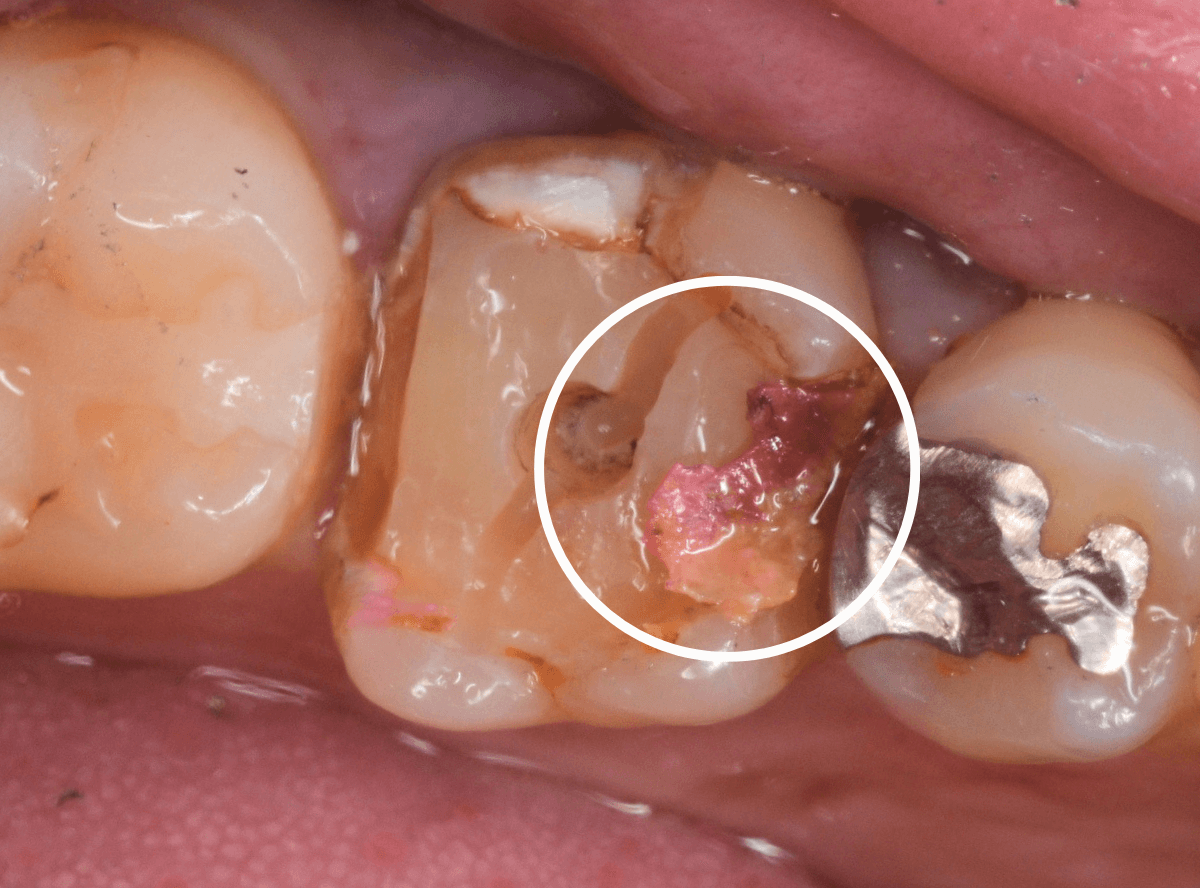

今回は、上の奥歯の銀歯(メタル・クラウン)の中で虫歯になってしまった方です。

通常は、さし歯の中が虫歯になってしまうと、レントゲンにも写らず見つけづらいのですが・・・。

歯を裏側から見たところです。

幸い、見える部分に虫歯が

さし歯と歯肉の間に虫歯ができているのがわかります。

歯の奥まで虫歯が進んでいるのか、浅い虫歯ですんでいるのかは治療をしながら調べていく必要があります。

さし歯を外すと、金属の土台(メタル・コア)が出てきました。

慎重に土台を外して、中を調べます。

赤く染色されている部分が虫歯の残っているです。

慎重に虫歯を除去して、土台の型を取ります。